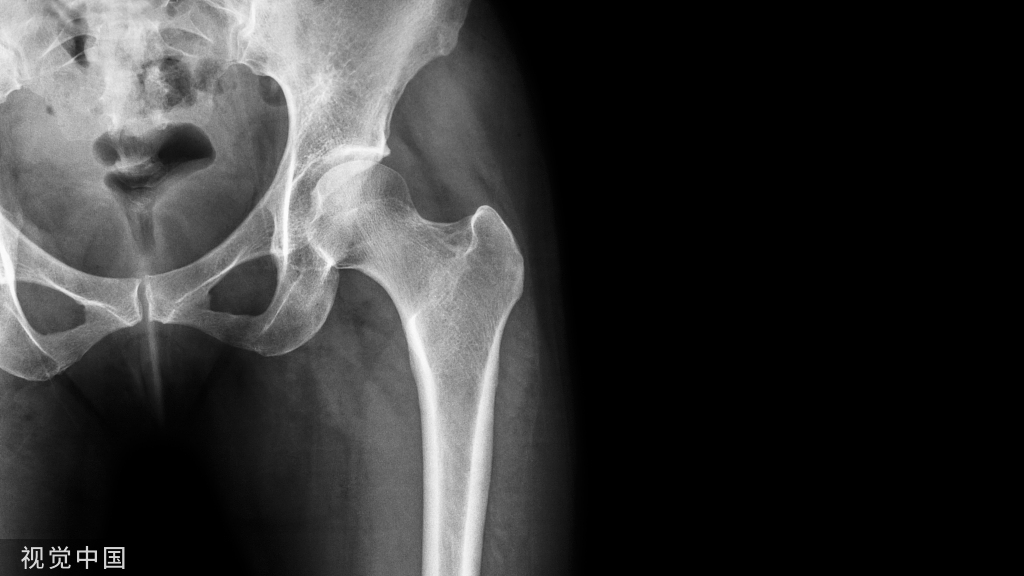

影像诊断:1、X线:早期髋臼上缘密度增高,股骨头凹边缘微小骨赘形成,继续发展可见较大骨赘,关节间隙上外侧非对称性狭窄,关节面边缘骨质增厚、关节面下假囊肿形成,重者出现股骨头半脱位,关节一般无骨质疏松,软组织无明显萎缩。(首选检查)

2、CT:髋臼前后唇、股骨头及髋臼窝边缘骨质增生,骨性关节面不规则硬化,关节间隙狭窄,承重面下出现假囊肿,关节腔可见积液及游离体。